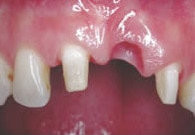

Früher die Regel

Ein fehlender Frontzahn wird nach Beschleifen der Nachbarzähne durch Einsetzen einer Brücke ersetzt.